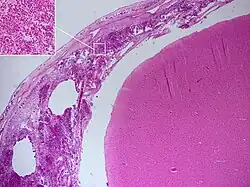

Postmortem

Meningitis can be diagnosed after death has occurred. The findings from a post mortem are usually a widespread inflammation of the pia mater and arachnoid layers of the meninges. Neutrophil granulocytes tend to have migrated to the cerebrospinal fluid and the base of the brain, along with cranial nerves and the spinal cord, may be surrounded with pus – as may the meningeal vessels.[57]